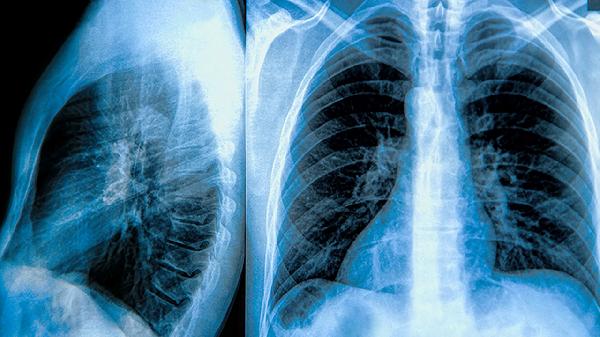

肺大泡术后需定期进行胸部CT检查,建议术后3个月、6个月及每年复查。日常生活中应避免剧烈运动、高压环境及呼吸道刺激物,坚持呼吸功能锻炼。若出现突发胸痛、呼吸困难等症状应及时就医排查复发可能。